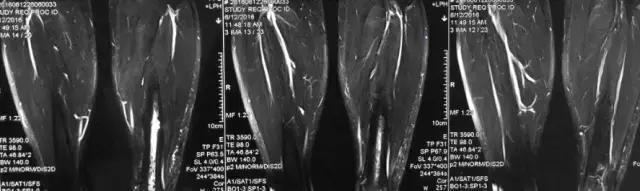

影像检查

诊断:感染。 检查:膝关节MRI,确认伤口窦道是否与髓腔相通。 治疗:1、血沉和C反应蛋白正常,目前无需特殊处理。 2、如果窦道反复出现或血沉和C反应蛋白升高可斟酌手术。如证明窦道与髓腔相通,需行扩髓。

核磁示中下段骨髓炎,上面切口处流脓,请问张主任你的意见要上手术吗?

北京积水潭医院张伯松:

1、是具备手术指征了!也就是说能够手术。 2、并不是必须马上手术。不发热,不红肿、化验都正常也能够换药口服抗生素。